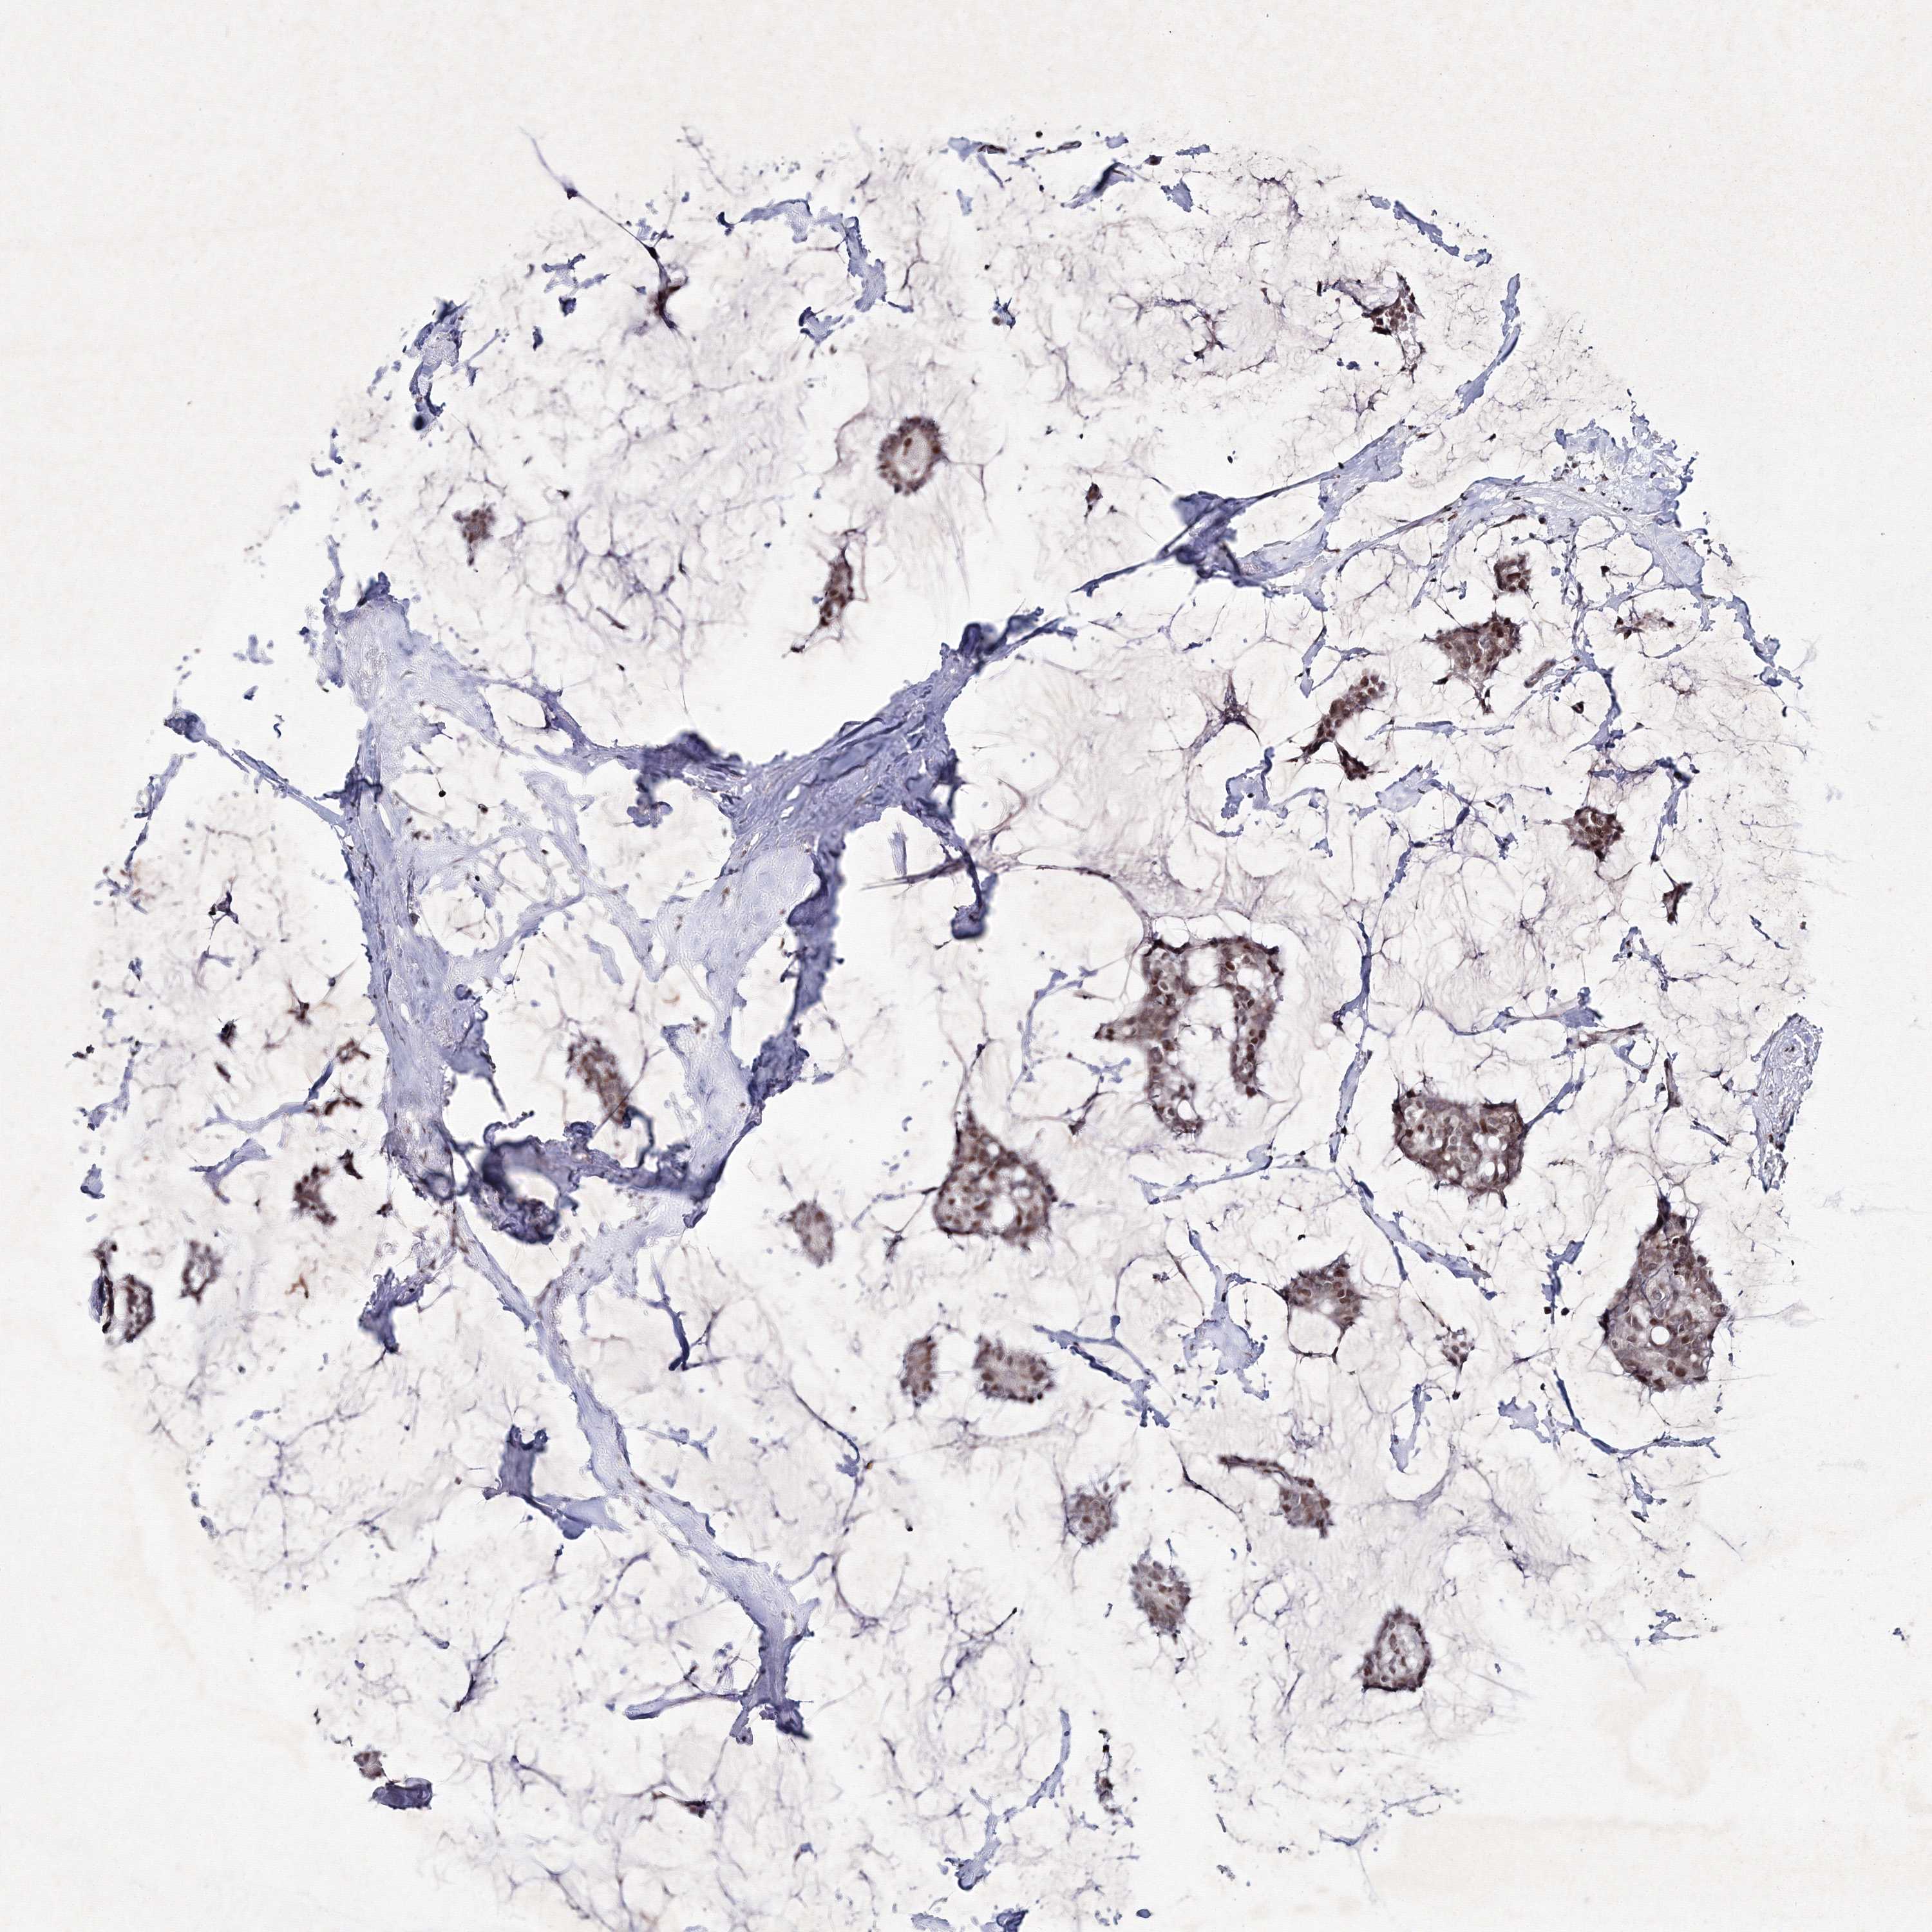

CANCER BREAST CANCER Show tissue menu

BRCA TCGA BRCA VALIDATION PROTEIN EXPRESSION

Breast cancer

Human cancer

Breast invasive carcinoma

SMIM29 is not prognostic in Breast Invasive Carcinoma (TCGA)